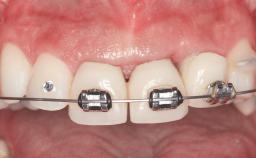

A 38-year-old woman presented with an esthetically unacceptable fixed partial denture replacing teeth 11, 21, 22. She had lost these teeth due to trauma when she was a child. The patient was not in pain but very concerned based on her previous experience that dental treatments had never satisfied her esthetic expectations. She was in good general health and reported no regular medications. No periodontal disease was noted despite the fact that the buccal flange of the prosthesis impeded cleaning of the tooth abutments. The patient did not smoke and complied with home maintenance requirements, as evidenced by her good oral hygiene status.